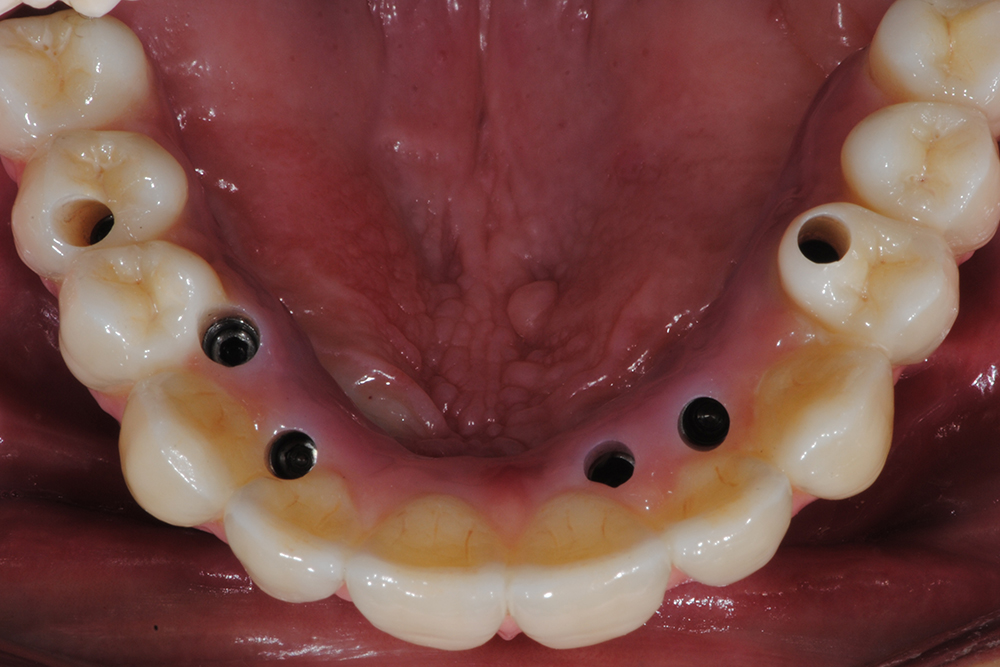

Ripristino dell'arcata superiore ed inferiore su impianti con ricostruzione estetica in zirconia e ceramica Category: Lavori ImpiantiMaggio 9, 2018Condividi questo ProgettoShare with FacebookShare with TwitterShare with Google+Share with PinterestShare with LinkedInProject navigationPreviousPrevious project:Ripristino dell’arcata superiore atroficaNextNext project:Protesi mobile superiore + Overdenture inferiore